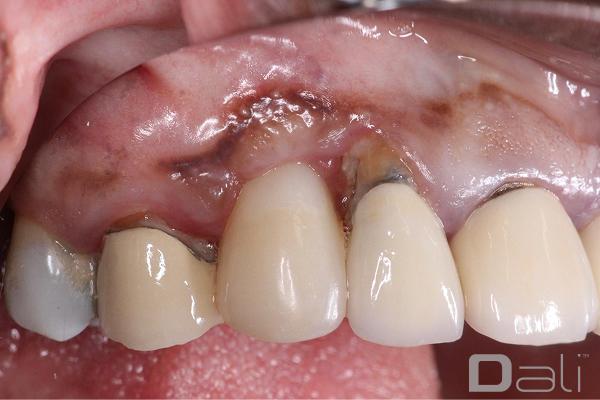

DALI Flex graft has the ability to stay in position and maintain space well. You can see from the post-operative pictures below, taken 2 years after the procedure, that the ridge contour and the tissue profile are ideal. Clearly, the DALI Flex Graft integrated well into the surrounding bone and tissue in a very healthy, and stable manner.

Following a GBR at the time of implant placement, a buccal ridge deficiency persisted. Surgical uncovery of the implant to expose the cover screw revealed successful bone regeneration around the implant, but a residual lack of ridge contour. Instead of using a traditional particulate graft covered with a resorbable membrane, a “flexible bone graft” sheet, DALI Flex Graft, was placed over the buccal plate to augment the buccal contour. Because the graft comes hydrated, it is easy to handle and adapt to the defect location. The flap was then pulled over the graft and adapted around the healing abutment. Following 6 weeks of healing, we see nice healing and an obvious increase in the facial contour.